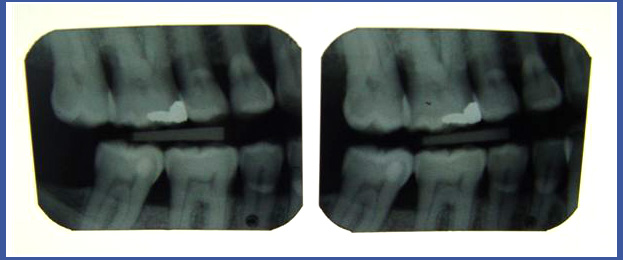

צילומי נשך:

בדרך כלל נעשים במרפאת שיניים – זהו הצילום המראה את החלק הכותרתי של השיניים הטוחנות והמלתעות בשתי הלסתות באותו צילום (במקרים רבים,יספיקו לרופא שני צילומים קטנים המבוצעים במקום), הצילום מאפשר לנו לראות נגעי עששת בחלק בין השניים ועל גבי משטחי הלעיסה של השיניים! בדרך כלל צילום נעשה בבדיקה שיגרתית אצל מתרפאים ללא בעיות של נסיגת עצם וחניכיים וללא כתרים על השיניים! בשיניים שיש עליהם כתרים, צילום נשך לא יספיק לצורך האבחנה ולכן יש לעשות צילום מסוג אחר.